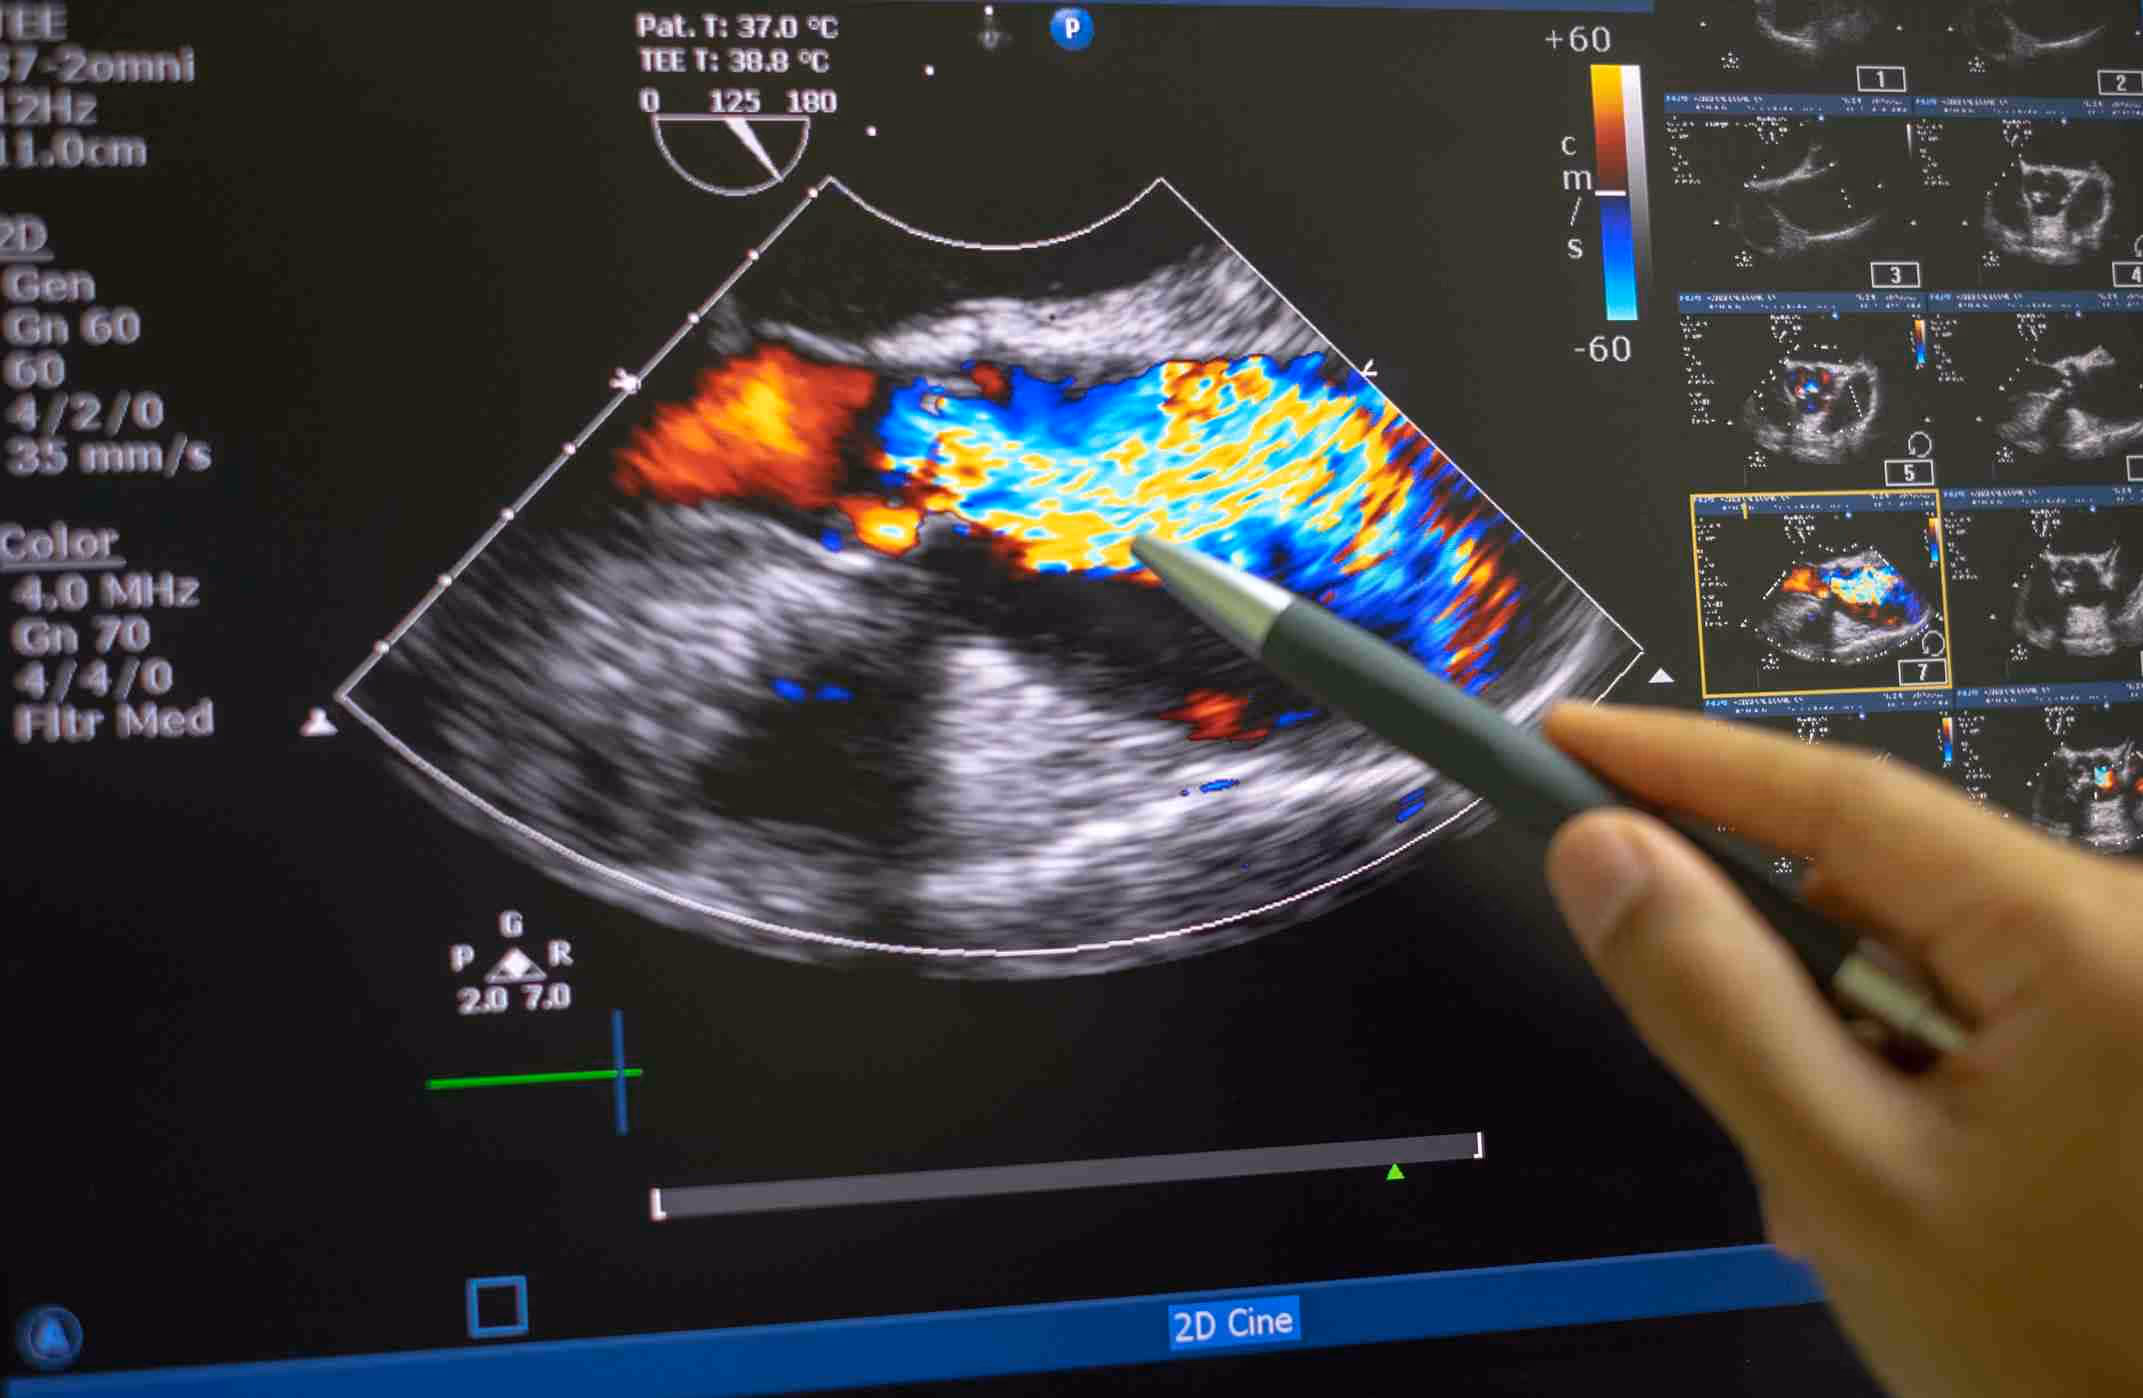

Uma vez que a função do doppler é atestar e medir movimentos aparentes, ele pode ser útil para aparelhos médicos que visam diagnósticos neste sentido. O maior uso do doppler em exames de imagem é por meio do ultrassom com doppler, também chamado de doppler venoso. Entenda melhor sobre este procedimento!

Ultrassom com Doppler

O ultrassom, um dos exames mais comuns e requisitados na clínica contemporânea, consiste em um exame de imagem que usa a tecnologia para a visualização em tempo real de órgãos do corpo. Muito comuns na região do abdômen e em gestantes.

A fase experimental da ultrassonografia é dos anos 40 aos 50, quando a tecnologia ainda estava em sua evolução inicial. Nos anos 60, o uso da tecnologia de ultrassom com doppler foi introduzida, incrementando um procedimento indolor e rápido, tornando-o também mais eficaz.

Levando em conta tudo o que explicamos sobre o efeito, o doppler venoso emite ondas sonoras que refletem, ou seja, fazem um eco, dando o nome comum de ecografia, — que significa as hemácias da corrente sanguínea para atestar o fluxo de sangue e se ele está correndo no sentido esperado.

A tecnologia é capaz de fazer isso, pois pode medir as ondas que são refletidas e determinar, baseada na frequência captada pelo efeito doppler, informações como:

- presença de trombose;

- veias ou artérias obstruídas;

- aneurismas e outros tipos de interrupção de fluxo.

Por meio deste procedimento, o profissional da Medicina obtém imagens médicas que, quando corretamente interpretadas, resultam em um exame resolutivo para o descobrimento de condições que devem ser tratadas.

Portanto, a relevância desse procedimento está em sua precisão e na boa performance em partes vitais do corpo, como é o caso da ecodopplercardiografia, imprescindível para detectar anormalidades no fluxo sanguíneo do coração.